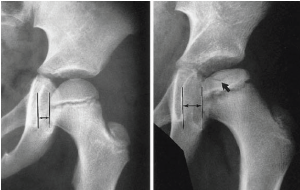

Q what is the name of this measurement? and what is the average + range?

A: Teardrop Distance

assesses the distance from the femoral head to the pelvic teardrop. The average is 9 mm, with a range of 6-11 mm.

A: Hip Joint Space Width

assesses the width of the hip joint space. The average is 4 mm, with ranges of 3-6 mm (superior), 3-7 mm (axial), and 4-13 mm (medial). The average for the medial joint space (teardrop distance) is 8 mm.